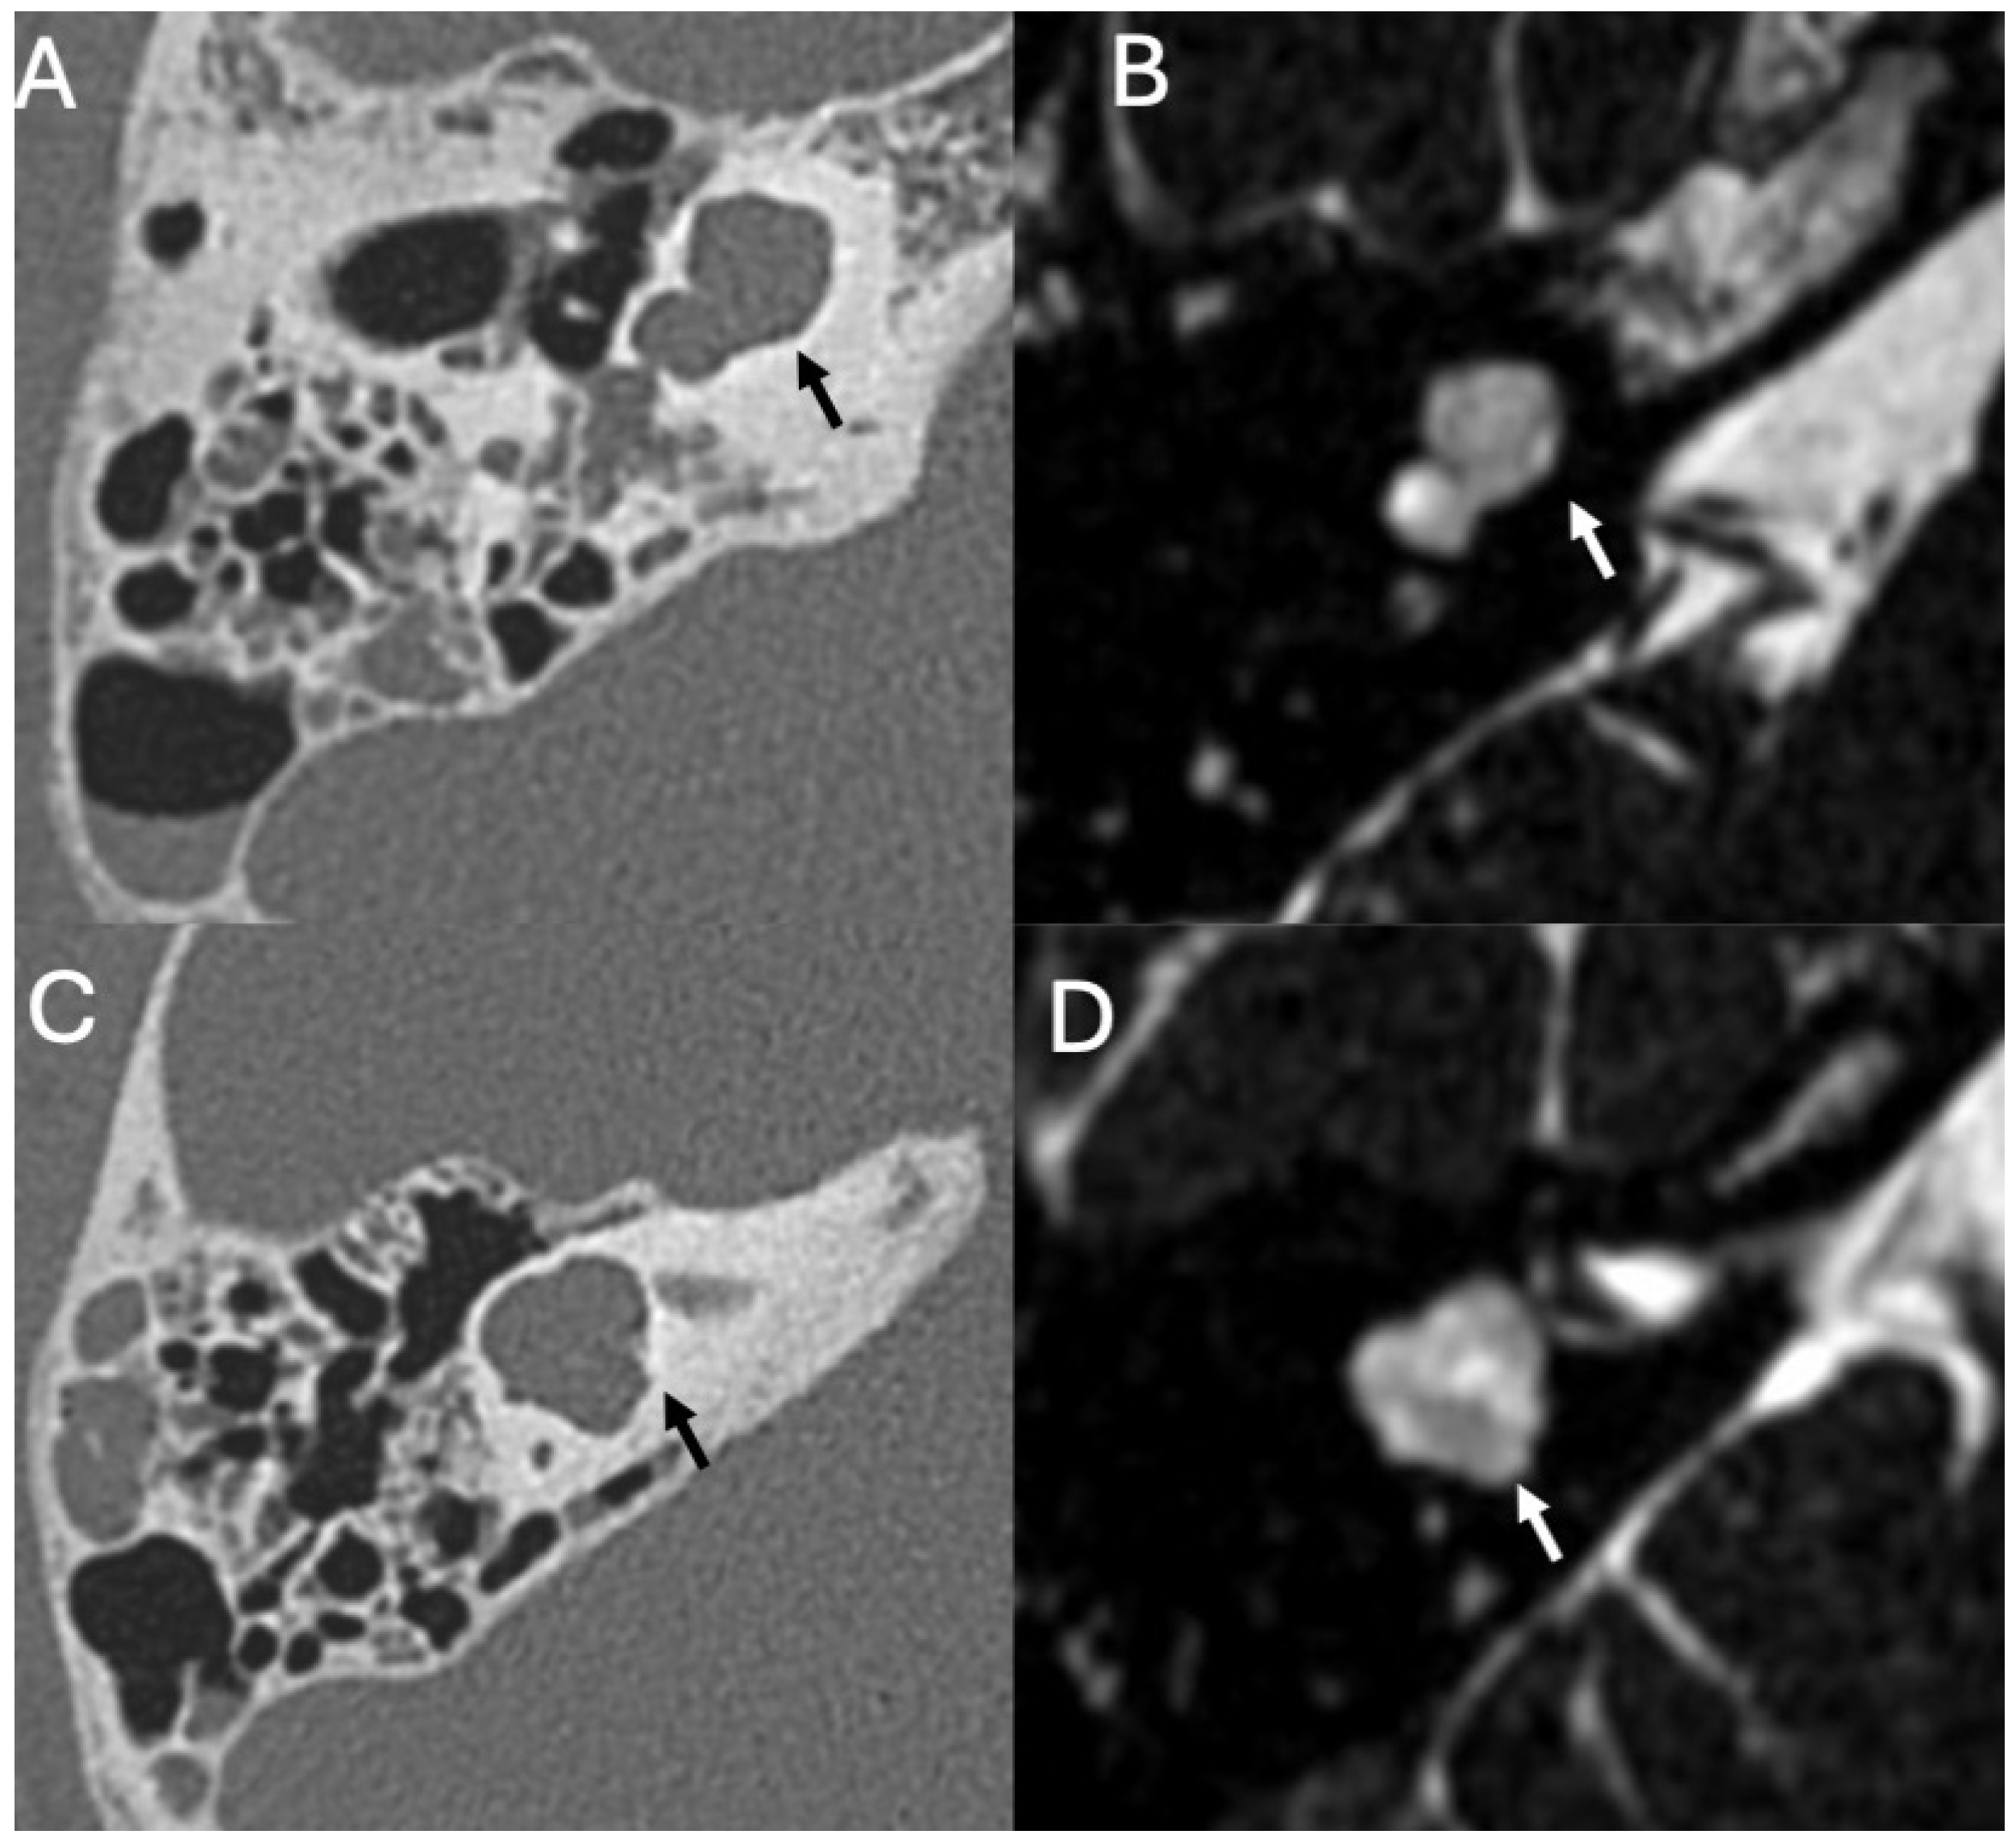

3.3.1. Imaging

3.3.2. Complications